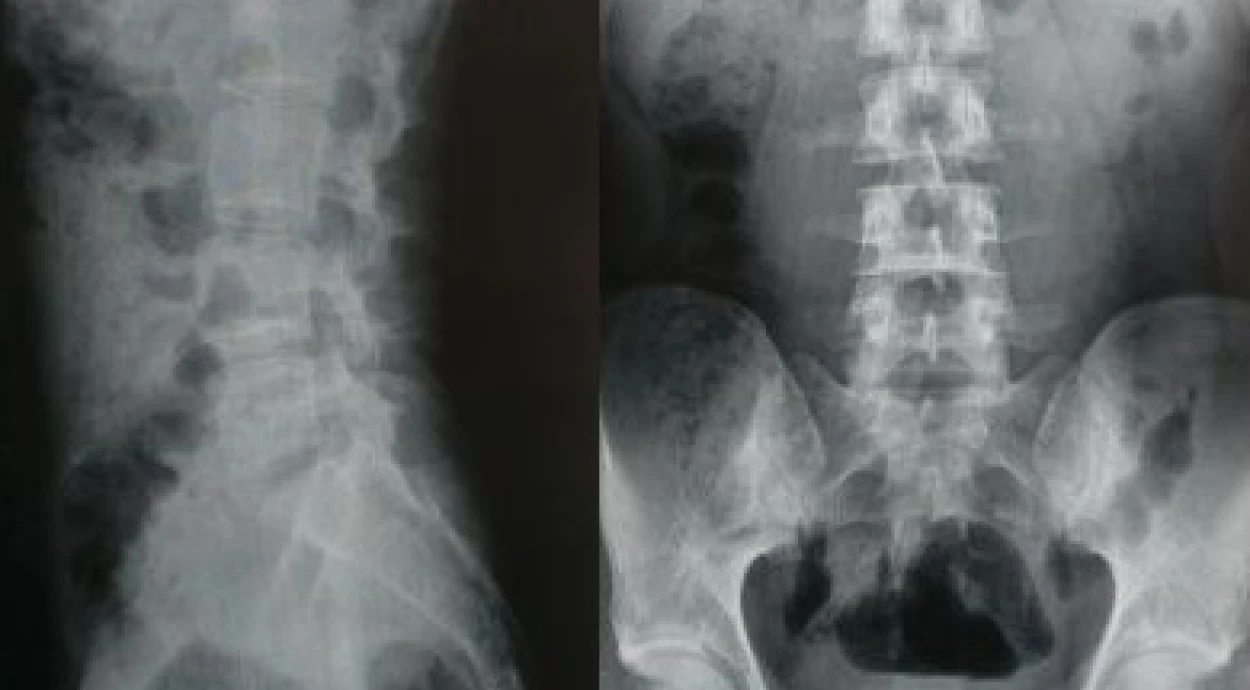

Рентгенографія — один із основних методів діагностики захворювань хребта. Зокрема, рентген поперекового відділу хребта дозволяє оцінити стан хребців, крижової ділянки та міжхребцевих проміжків, а також виявити наслідки травм, дегенеративні зміни та інші порушення.

Рентгенографія попереково-крижового відділу хребта дозволяє оцінити стан кісткових структур нижньої частини хребта та виявити зміни, які можуть бути причиною болю або обмеження рухливості. Під час дослідження лікар аналізує положення хребців, їхню форму, висоту та взаємне розташування.

Що видно на рентгені попереково-крижового відділу

Під час аналізу рентгенівських знімків лікар детально оцінює анатомічну будову попереково-крижового сегмента хребта, положення хребців та особливості їхньої структури. Дослідження дозволяє виявити різні структурні зміни кісткових тканин.

На рентгенограмі попереково-крижового відділу можуть бути помітні:

- зміни форми та структури тіл хребців;

- деформації або зміщення хребців;

- ознаки компресійних ушкоджень після травм;

- вроджені аномалії розвитку хребта;

- кісткові розростання (остеофіти);

- ущільнення або інші зміни кісткової тканини;

- особливості будови крижової кістки та крижово-клубових з’єднань.

Такі зміни допомагають лікарю оцінити стан попереково-крижового відділу хребта та визначити, чи потрібні додаткові обстеження для уточнення діагнозу і вибору подальшої тактики лікування.